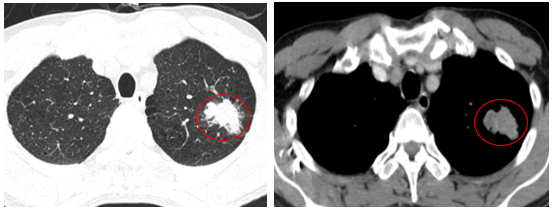

-         Chụp cắt lớp vi tính lồng ngực (06/2025): Nhu mô đỉnh phổi trái có khối tổ chức kích thước ~35x25mm, bờ không đều, có cắt cụt một số nhánh phân thùy đỉnh, ngấm thuốc mạnh không đồng nhất sau tiêm. Thuỳ trên và dưới có nốt đặc nhỏ đường kính 2mm.

Hình 1: Nhu mô đỉnh phổi trái có khối tổ chức kích thước ~35x25mm, bờ không đều, có cắt cụt một số nhánh phân thùy đỉnh, ngấm thuốc mạnh không đồng nhất sau tiêm

- Chụp cắt lớp vi tính lồng ngực (09/2025): Nhu mô thùy trên phổi trái có khối tổ chức kích thước ~39x23mm, bờ không đều, có cắt cụt một số nhánh phân thùy đỉnh, ngấm thuốc mạnh không đồng nhất sau tiêm (tăng nhẹ kích thước so với phim chụp CLVT cũ 06/2025).

Hình 6: Nhu mô thùy trên phổi trái có khối tổ chức kích thước ~39x23mm, bờ không đều

Nhận xét: Khối u phổi trên phim cắt lớp vi tính ngực (09/2025): : ~39 ×23 mm → tăng nhẹ về kích thước so với trước (35 × 25 mm), chỉ điểm u: Cyfra21-1 tăng từ 4,6 ng/ml lên 6,07 ng/ml → gợi ý bệnh ổn định Stable Disease (SD),khối u vẫn ở giai đoạn cT2N0M0. Bệnh nhân đã được hội chẩn đa chuyên khoa, có chỉ định phẫu thuật cắt thùy phổi và nạo vét hạch.